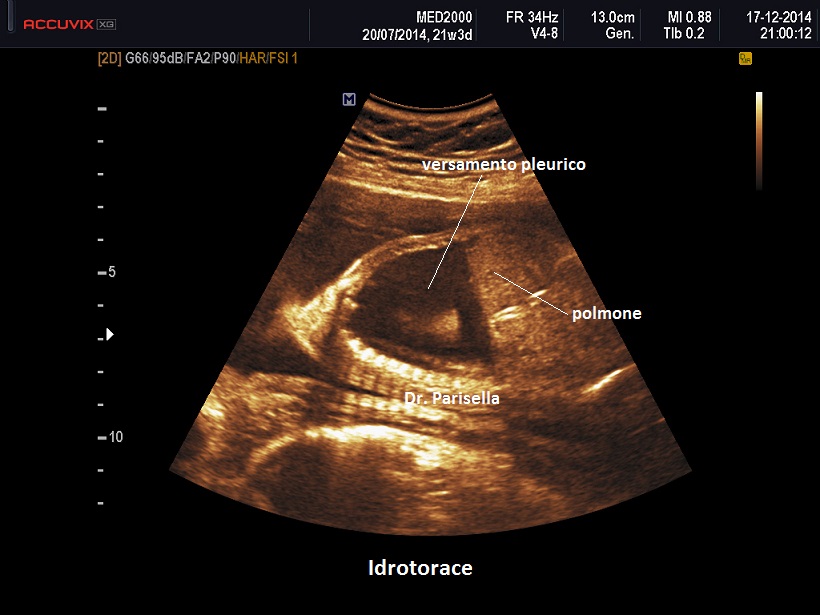

Idrotorace

L'Idrotorace è una raccolta liquida a livello della cavità pleurica. Può presentarsi in forma monolaterale o bilaterale; può essere isolato o associato ad idrope.

La diagnosi ecografica non offre in genere difficoltà ed è rappresentata da un versamento pleurico monolaterale o bilaterale.

Nelle forme monolaterali si ha shift mediastinico con dislocazione controlaterale del cuore.